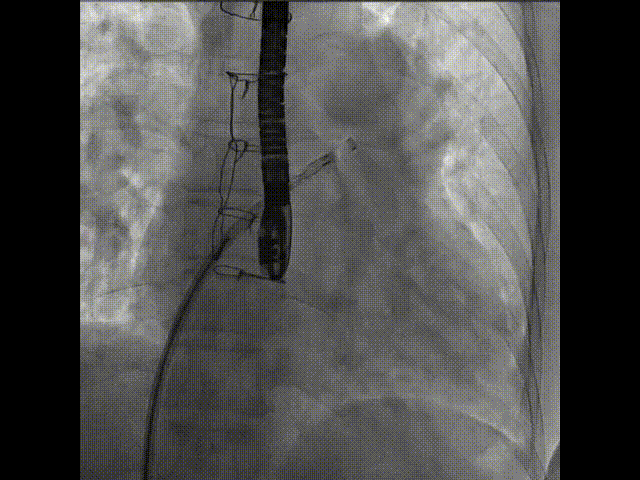

術中首先在局麻下穿刺股動脈、股靜脈,完成心導管檢查評估后轉為全麻,在食道超聲引導下穿刺房間隔,穿刺成功后將加硬導絲送入左上肺靜脈建立軌道,根據患者病情行球囊預擴張后植入6mm孔徑房間隔造孔支架,經透視及食道超聲評估支架左右盤展開良好,夾持于房間隔兩側,固定穩(wěn)定、位置良好,食道彩超顯示房水平右向左為主分流,分流孔直徑符合預期大小,心導管檢查評估達到預期效果,釋放造孔支架。術后12h患者下床活動,恢復順利,擬于近日完善術后評估后出院。